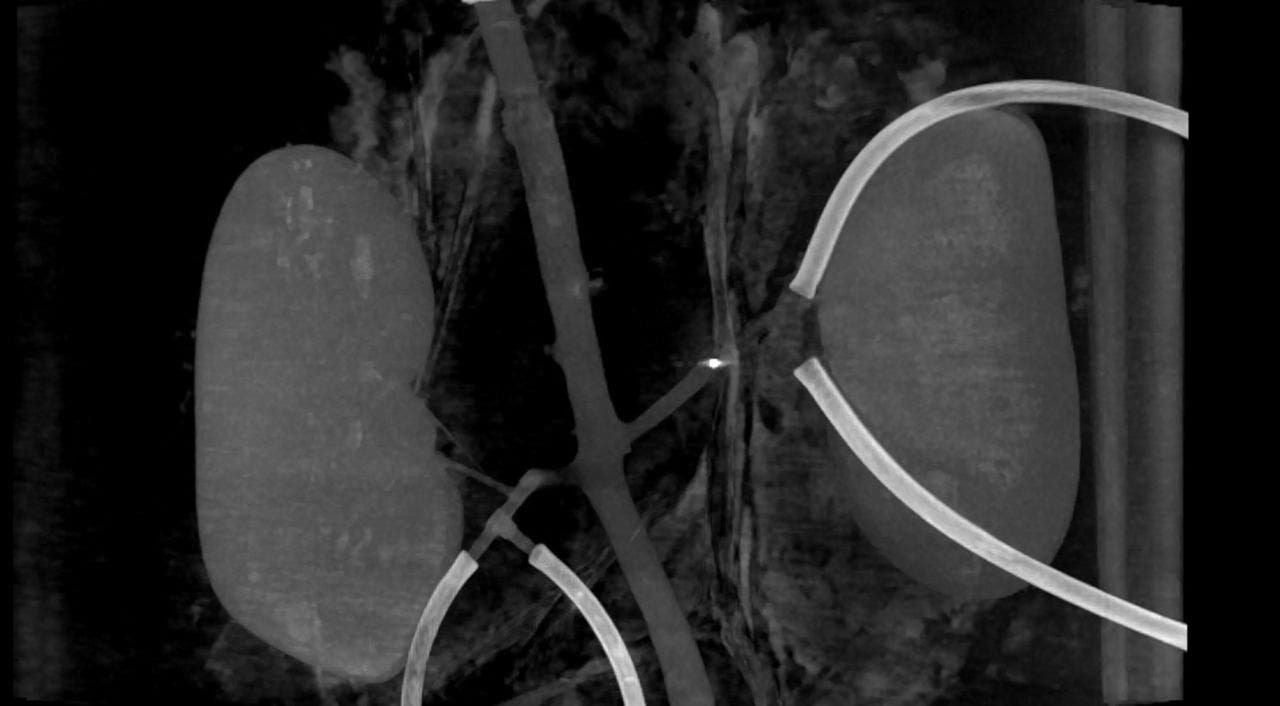

At the Technical Medical Centre of the University of Twente, the researchers set up their experiment with a real aorta and kidneys. The scientists were able to guide multiple millirobots through the vessels and break up clots. They think the millirobots could work even better with a stronger external magnet.

A lab setup utilized in the study to treat blood clots. (University of Twente)